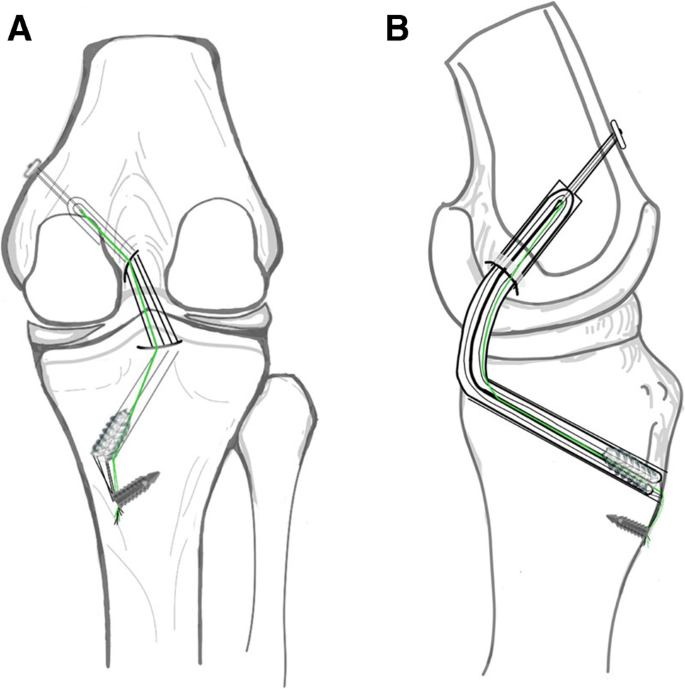

3.3. Phẫu Thuật Thay Thế Khớp (Arthroplasty)

Khi các phương pháp bảo tồn thất bại và chất lượng cuộc sống bị suy giảm nghiêm trọng do đau đớn và mất chức năng (thường gặp trong thoái hóa khớp giai đoạn cuối), phẫu thuật thay khớp (toàn bộ hoặc bán phần) là lựa chọn tối ưu. Sự tiến bộ trong vật liệu cấy ghép và kỹ thuật phẫu thuật ít xâm lấn đã cải thiện đáng kể tỷ lệ thành công và thời gian phục hồi của bệnh nhân.